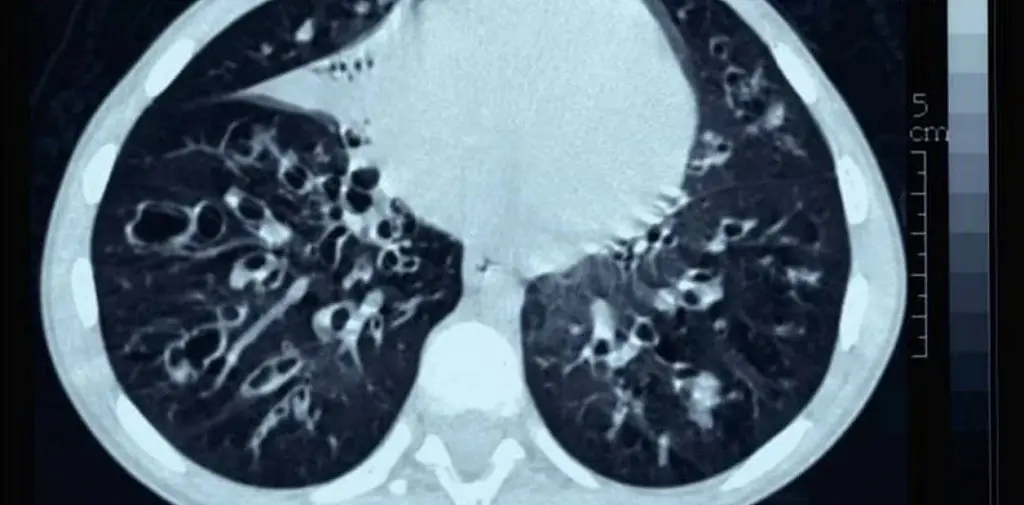

Oscar Rizzo, neumonólogo del Hospital de Rehabilitación Respiratoria María Ferrer, explicó las características que tiene la enfermedad “es progresiva y afecta al páncreas, el pulmón, senos paranasales, hígado, intestinos, piel y sistema reproductivo”.

Ocasiona un compromiso multisistémico, con "complicaciones infecciosas, respiratorias, malabsorción, desnutrición, deshidratación, esterilidad y conlleva problemas psicosociales sobre todo en los años de desarrollo madurativo”, agregó Rizzo.